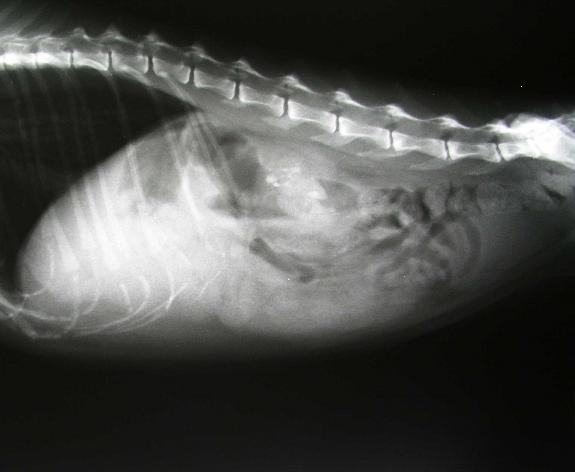

If your beloved cat has a problem that needs medical attention, radiology is one of the most effective diagnostic tools available. We can see if your cat swallowed something that is causing a problem. We can also tell if your cat has other internal issues, like a tumor, fractured bones, or other developing medical problems that need attention.

- Radiographs: We commonly refer to these as “X-rays” and they can help your veterinarian to distinguish internal organs, identify injuries, and locate foreign objects inside your pet.